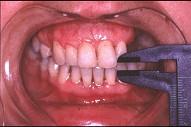

问题 关于颞下颌关节强直(如图)的描述哪项是正确的()

选项 A.颞下颌关节强直常常突然发生 B.关节及关节周围组织器质性病变造成开口困难或完全不能开口 C.颞下颌关节内强直是关节内骨性黏连 D.颞下颌关节外强直是关节外纤维黏连 E.混合性下关节强直是指关节内,外强直同时发生,又称颌间挛缩

答案 B